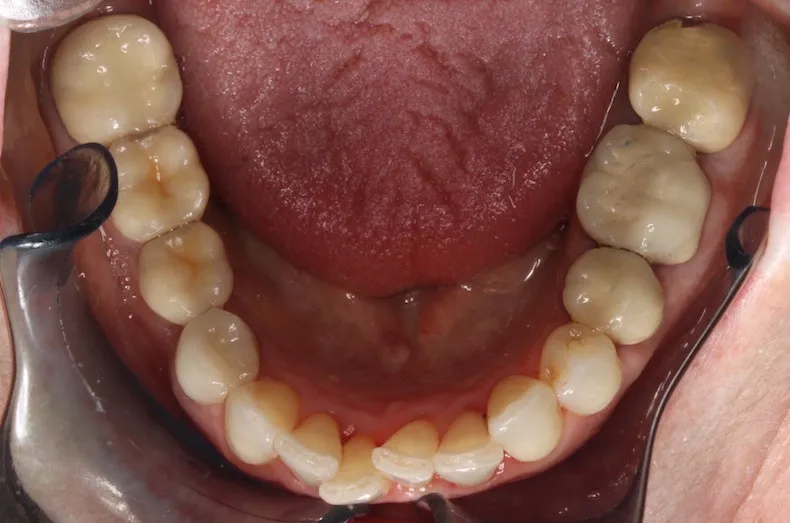

Case Study #1: 20 months of Invisalign for better alignment and bite.

Case Study #2: Invisalign for Crowding and To Widen Arches, 22 months

Case Study #3: Invisalign for Teeth Crowding

Case Study #4: Invisalign for Rotations/Crowding

Case Study #5: Short Course Invisalign for 8 Months

Case Study #6: 24-Month Invisalign Treatment

Case Study #7: 20 months of Invisalign to correct front crossbites. A crossbite is when one or more top teeth sit behind the bottom teeth

Case Study #8: Invisalign for 21 months to fix an anterior open bite

Case Study #9: 28 months of Invisalign for better alignment and bite.